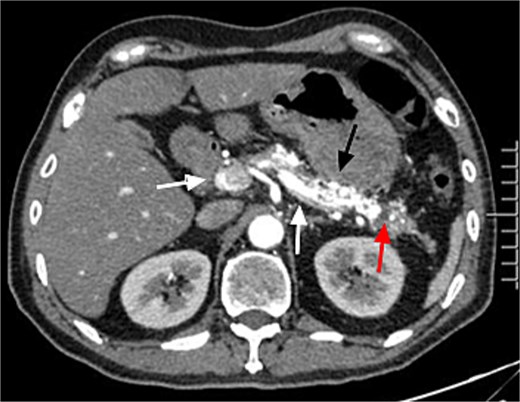

A 45-year-old man with upper abdominal pain for 3 days was referred to our unit. His past history was unremarkable. Upon physical examination, He had abdominal tenderness. Routine blood test showed elevated amylase and lipase (395.8 and 536.7 U/l). Enhanced computed tomography (CT) demonstrated tortuous dilated arteries in the pancreas body and tail with a small pseudocyst, and early opacification of the portal vein, but no signs of portal hypertension (Fig. 1). Endoscopy revealed no varices and ulcers. Based on these findings, a diagnosis of PVAM with AP was made.

Enhanced CT showed tortuous dilated arteries in the pancreas body and tail (black arrow) with a small pseudocyst (red arrow) and early opacification of the splenic vein and portal vein (white arrows).